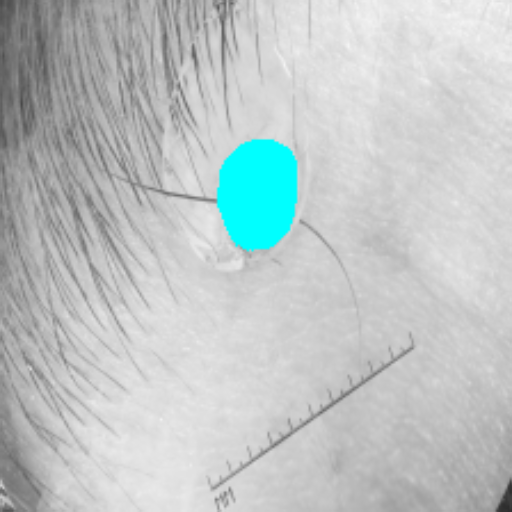

Figure 3 presents a qualitative comparison of segmentation performance on examples from the Synapse, BTCV, ACDC, and ISIC17 datasets. The first two examples (from Synapse) highlight variations in segmentation performance among U-Net, TransUnet, Mamba-Unet, and Swin-Unet. While Swin-Unet performs well in the first example, its performance decreases in the second example, particularly in segmenting the organ highlighted in blue. Additionally, it misclassifies background regions as the class highlighted in orange. In contrast, our approach demonstrates high robustness in segmenting all classes accurately and aligning well with the ground truth masks.

Across BTCV, ACDC, and ISIC17, the comparison methods exhibit varying performance depending on the task and class. For instance, Mamba-Unet struggles to segment multiple organs in BTCV, even misclassifying certain classes as others. In the ACDC dataset, both TransUnet and Mamba-Unet perform poorly in segmenting the three classes. In the last column (ISIC17), Swin-Unet oversegments the skin lesion compared to the ground truth. Unlike the comparison models, our approach consistently delivers effective segmentation across different tasks and datasets.

These qualitative findings further reinforce the quantitative results presented in the experimental section, demonstrating the effectiveness of our MambaCAFU model in handling binary and multi-class segmentation across diverse medical imaging modalities and tasks.

Slice GT Unet TransUnet Mamba-Unet Swin-UMamba MambaCAFU-V1

Figure 3: Visual comparison of segmentation examples from Synapse (first two examples), BTCV (3-4 examples), ACDC (5th example) and ISIC17 (last example). Columns: input slice, ground truth, Unet, TransUnet, Mamba-Unet, Swin-UMamba, and MambaCAFU-V1.